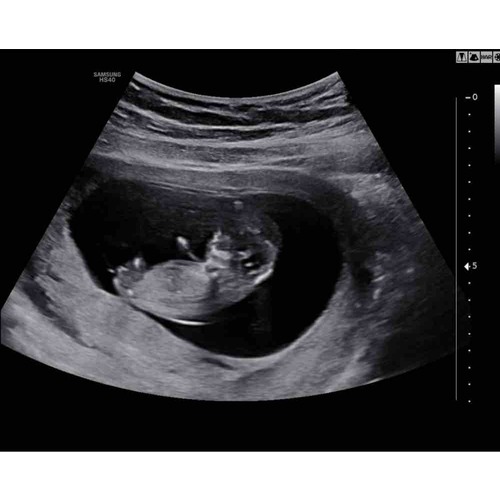

Ik heb hier een echo van 13.6 weken..Iemand die hier iets ziet!?

Nub is niet te zien voor mij, maar qua skull theorie denk ik een jongetje 😅

🤗 echo van 12 weken!

Meisje denk ik

Ik zie wel weer duidelijk een jongen